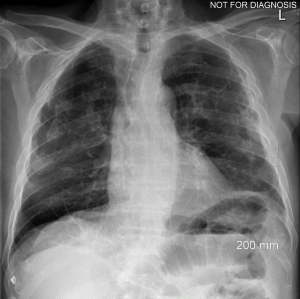

A construction worker presents with a dry cough, can you diagnose this patient?